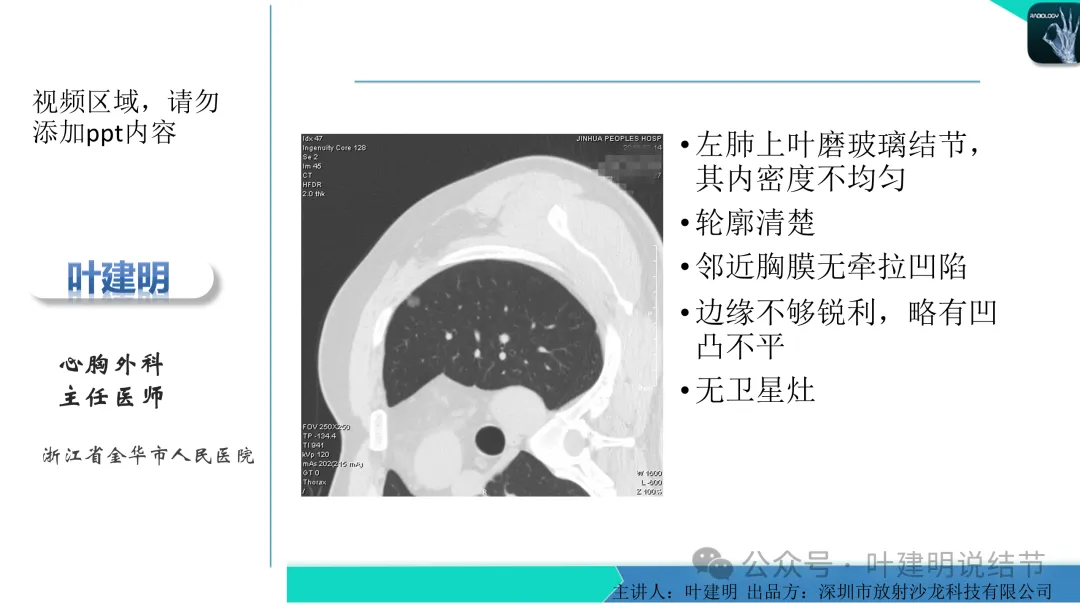

当地说考虑微浸润性腺癌的左下主病灶影像连续层面展示:

这个病灶会是微浸润性腺癌吗?当然没有病理诊断,我也不能说百分之百必不会,但这样的病灶已经风险大到必得尽快手术切除干预了吗?显然还早着呢:1、影像不是典型的结节状;2、边缘与轮廓模糊不清;3、灶内似有细支气管扩张(更容易是细支气管扩张伴少许周围炎或肺泡上皮增生);4、血管邻近走但无牵拉影响;5、没有实性成分,没有锐利毛刺,没有胸膜牵拉,没有血管进入,没有任何倾向风险性高的影像特点。我一直强调:肺结节是否要干预处理,不要纠结于最后病理是什么,而要看风险高低;而风险高低的最重要术前判断依据一是随访有无进展,二是有没有实性成分。只要没有肉眼可见的影像上的实性成分,风险就是低的!何况病理也是人看的,原位还是微浸润,不典型增生还是原位有时也在一念之间。

早在2020年时,我受邀在《放射沙龙》做过一个系列的精品课,当时专门总结分析过各类良恶性肺结节与肿块的影像特征,这是当时关于微浸润性腺癌影像特征的分析,今天看来仍基本不太需要改变,大家有兴趣的可以参考: